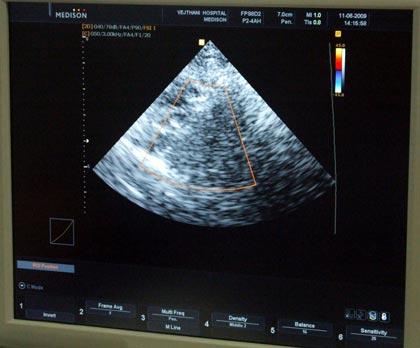

นายแพทย์ชยานุชิต ชยางศุ อายุรแพทย์โรคสมองและระบบประสาท โรงพยาบาลเวชธานี กล่าวถึงวิธี Carotid Duplex Ultrasounds ซึ่งเป็นการตรวจหาโอกาสเสี่ยงของการเกิดอัมพฤกษ์/อัมพาต ว่าเป็นการตรวจหลอดเลือดใหญ่ที่คอ ที่ไปเลี้ยงสมองส่วนหน้า และตรวจหลอดเลือดที่ไปเลี้ยงสมองส่วนหลังด้วยคลื่นเสียงความถี่สูง เพื่อดูการไหลเวียนเลือดที่ขึ้นไปเลี้ยงสมอง และตรวจหลอดเลือดว่ามีคราบหินปูน หรือคราบไขมันเกาะอยู่ภายในหลอดเลือดหรือไม่ และสามารถวัดขนาดของคราบดังกล่าวได้ เพราะเมื่อมีการหนาตัวมากขึ้น จะทำให้เลือดไหลเวียนไม่สะดวก และอาจทำให้เส้นเลือดที่ขึ้นไปเลี้ยงสมองเกิดการตีบหรือตัน การตรวจนี้สามารถช่วยประเมินผู้ป่วยที่เป็นโรคอัมพาต และช่วยในการวินิจฉัย ติดตามสภาพของหลอดเลือดในสมองของผู้ป่วย ในขณะที่ผู้ป่วยอยู่ในห้องผู้ป่วยหนักได้

นายแพทย์ชยานุชิต กล่าวทิ้งท้ายว่า การตรวจด้วยเครื่องมือ Carotid Duplex Ultrasounds เป็นการตรวจเบื้องต้นเท่านั้น โดยการตรวจดังกล่าว ควรต้องอยู่ในความดูแลของแพทย์เฉพาะทางด้านอายุรกรรมประสาท